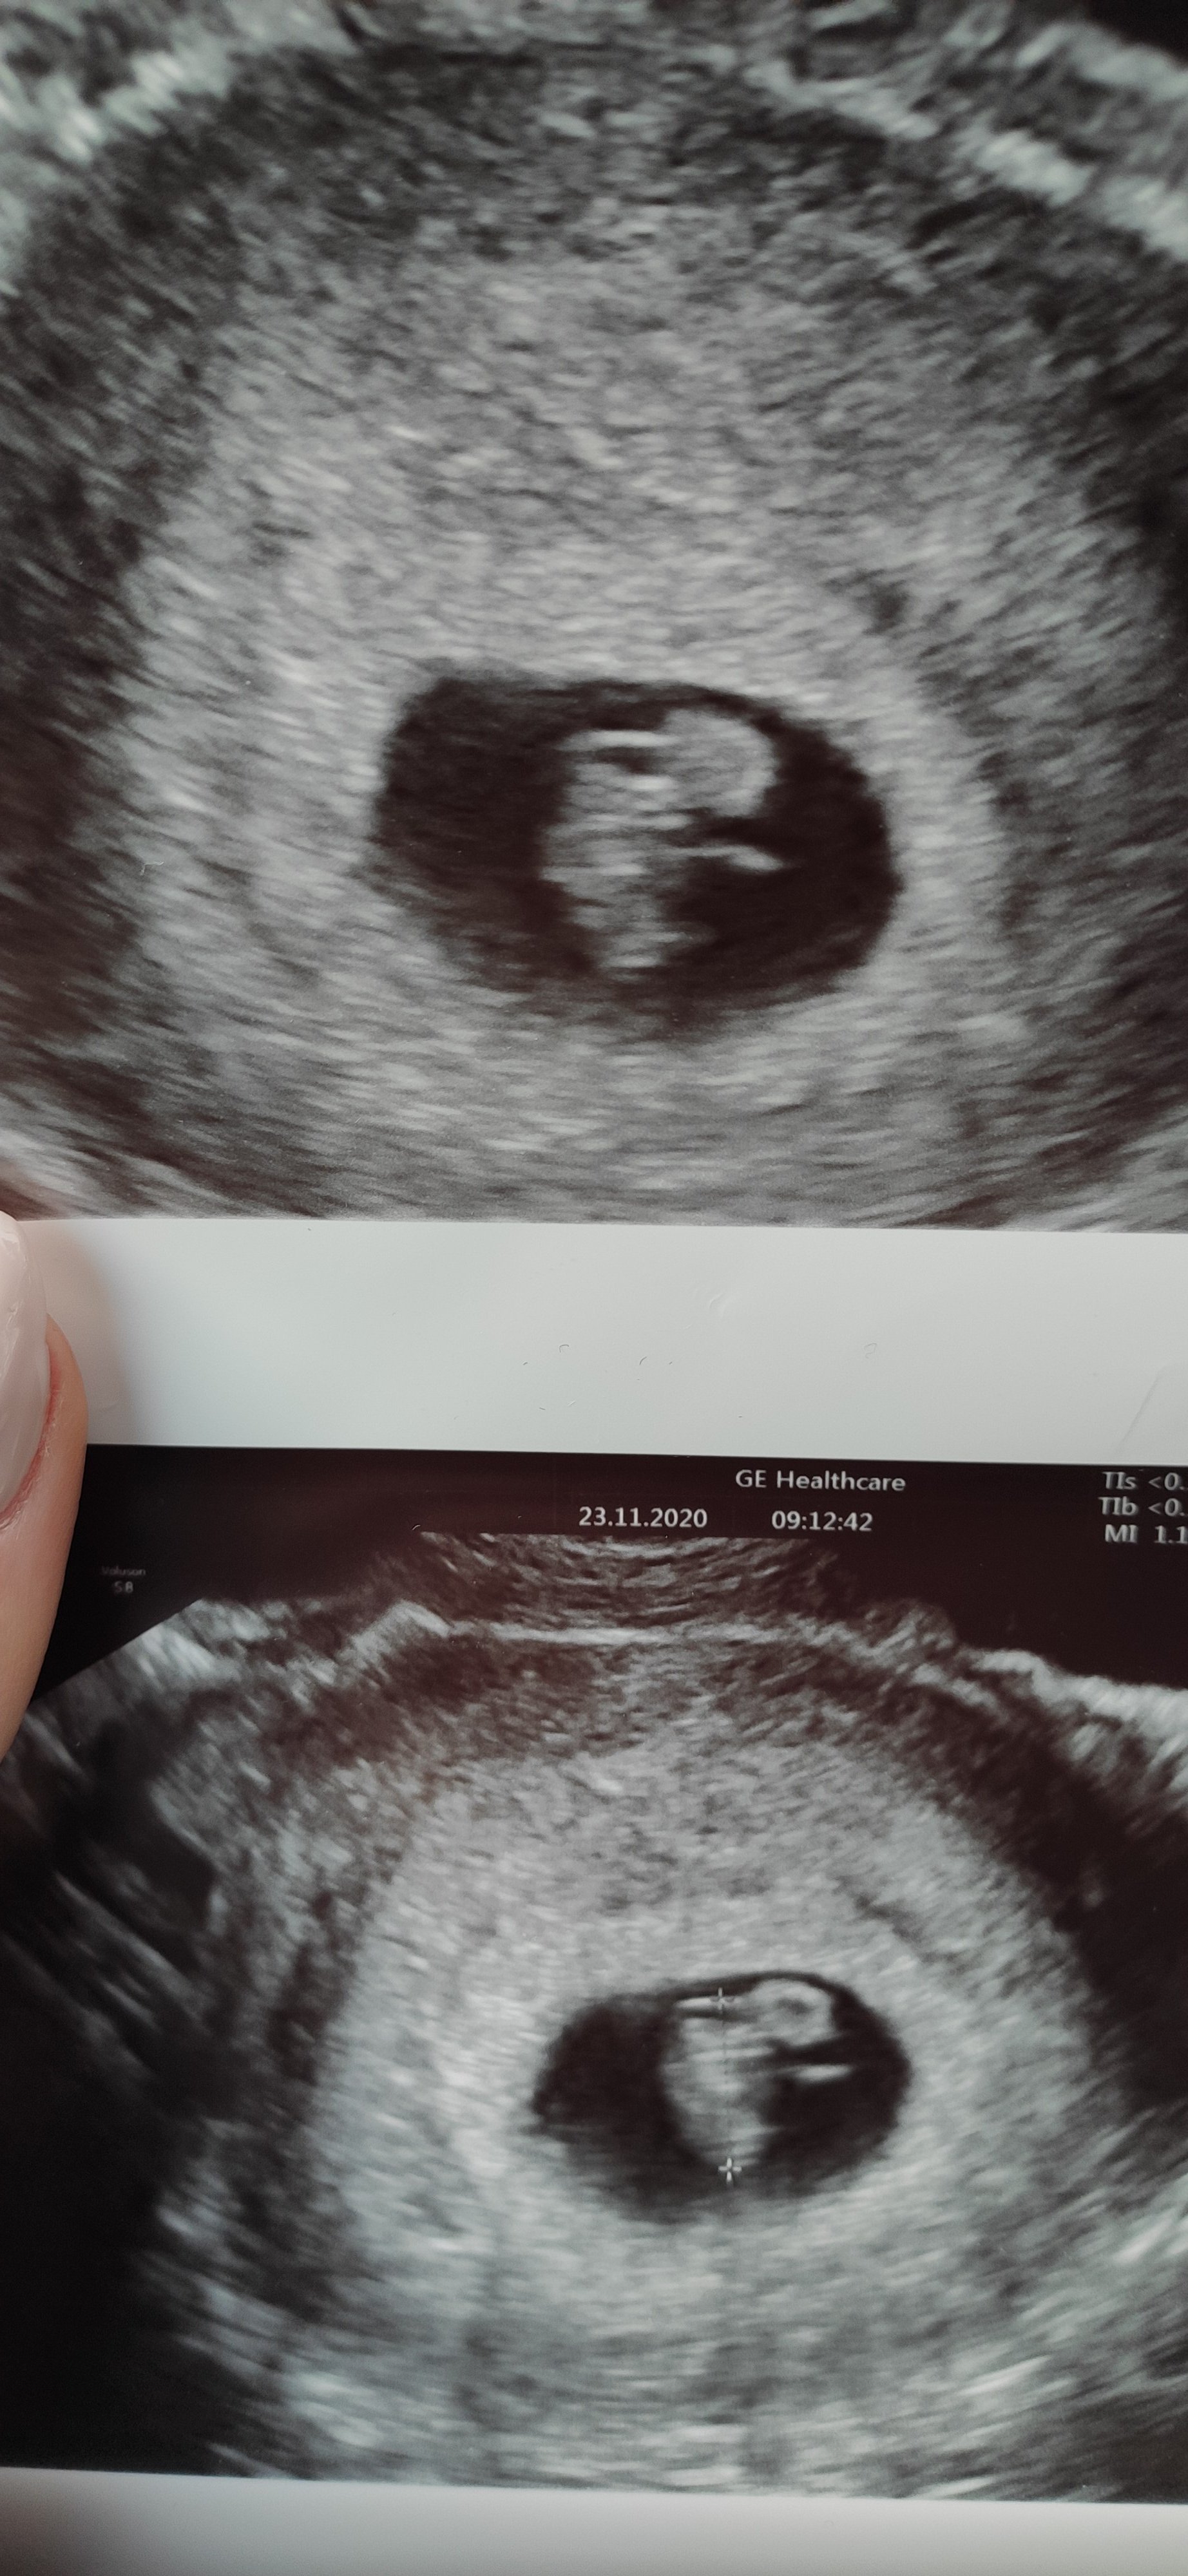

Ja dziś byłam na wizycie i serduszko pięknie bije

Zobacz załącznik 1205324

Gratuluje udanej wizyty! Piekne zdjęciaHey dziewczyny nadrobiłam